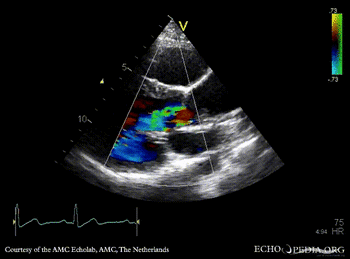

PLAX: dilated aortic root and left ventricle PLAX with Color Doppler: severe aortic regurgitation